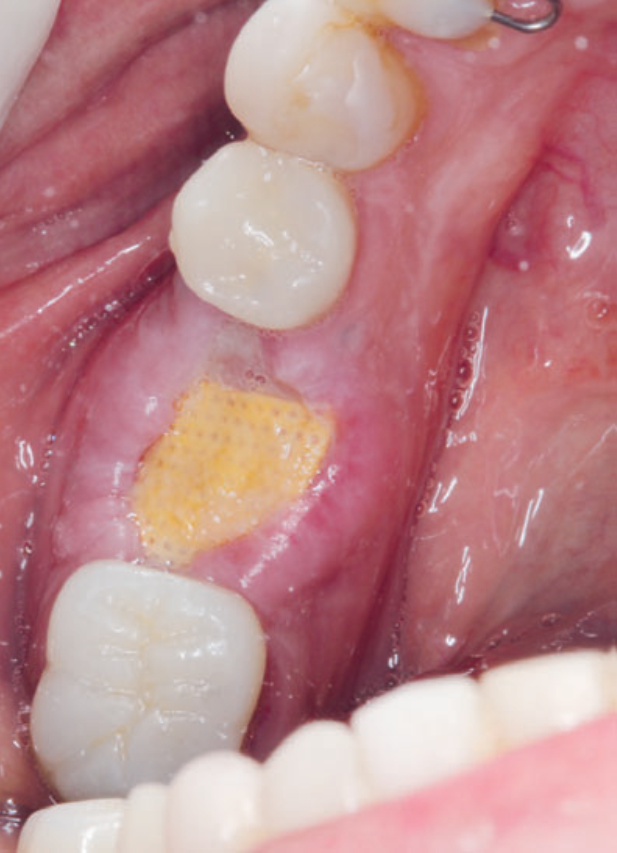

Para a regeneração óssea guiada, o substituto ósseo natural composto por hidroxiapatita bovina e colágeno do tipo I (Extra Graft XG-13) foi introduzido ao redor do implante para preenchimento do GAP (Figura 7). Depois, uma barreira regenerativa não absorvível (Cytoplast) foi recortada, adaptada e colocada, seguida por uma membrana biológica bovina (Figuras 8 e 9). O procedimento cirúrgico foi finalizado com a realização da sutura com fio de nylon 5.0. Para verificar o posicionamento do implante dentário, uma radiografia periapical foi realizada imediatamente à cirurgia (Figura 10).

Neste relato de caso, a remoção da membrana Cytoplast foi feita aos 15 dias do pós-operatório. Depois de 23 dias, foi realizado o acompanhamento da cicatrização local (Figuras 11 e 12). Seis meses depois, a paciente voltou para realizar a reabertura da área cirúrgica (Figura 13) e retirada do parafuso de cobertura, visando à fase da reabilitação protética. Após a reabertura e remoção do parafuso de cobertura (Figura 14), e uso do Túnel Check para prótese cone-morse (estojo protético Implacil De Bortoli), foi selecionado o cicatrizador com dimensões de 4,5 mm x 5,5 mm (Figura 15) para guiar o condicionamento gengival (Figura 16). A reabilitação protética ainda está em andamento para finalização do caso (Figura 17).